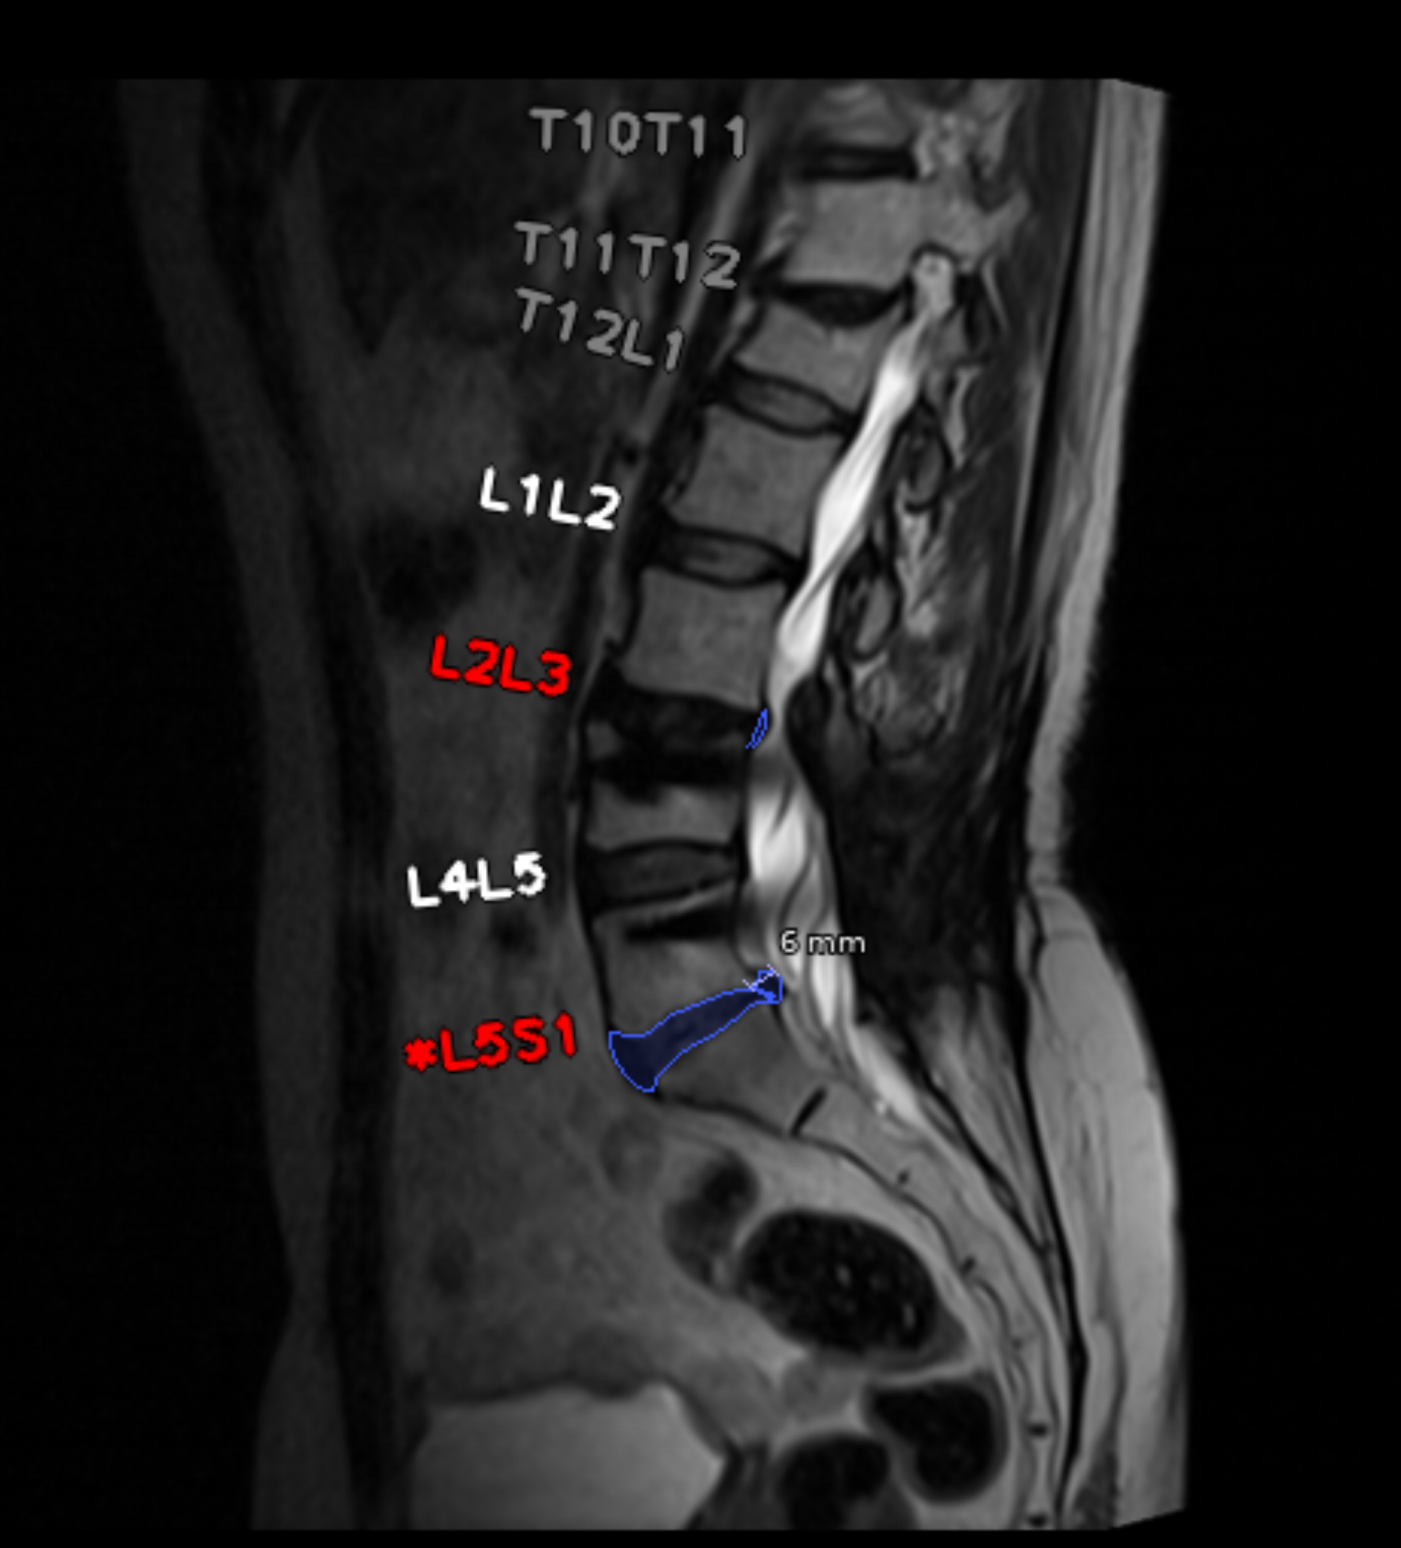

IA para Resonancia Magnética Lumbar

Esta solución impulsada por IA proporciona mediciones automáticas y objetivas para patologías de columna lumbar, facilitando diagnósticos más consistentes.

Hernia, protrusión y extrusión discal.

Estenosis espinal central y congénita.

Impacto radicular y alteraciones vertebrales.

Mediciones objetivas de lordosis y diámetro aórtico.